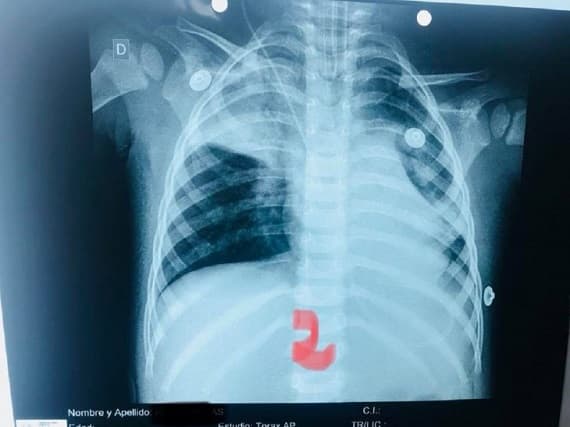

Semilla de mandarina casi causa muerte de niño por asfixia

La madre del niño lo trasladó de urgencias al Hospital Regional de Concepción.

El médico manifestó que tuvo que realizar una broncoscopía de urgencia y que el pequeño se salvó de morir “de milagro”.

Señaló además que durante el procedimiento, la semilla se movió al otro pulmón, lo que pudo haber sido fatal, ya que le causó un cuadro de neumonía.

“Fue una situación gravísima, pero el niño está bien y recuperándose en terapia intensiva”, remarcó.

Indicó que durante todo el procedimiento el paciente estuvo con asistencia respiratoria artificial, porque ya no respiraba por sí mismo.

Las semillas pueden tener, en promedio, entre tres y 10 milímetros, mientras que el diámetro de la tráquea de los pequeños y pequeñas de 1 a 6 meses de vida mide de cinco a seis milímetros; de 6 a 18 meses mide seis a siete milímetros; de 1 y medio a 4 años, siete a ocho milímetros, y de 4 a 6 años, ocho a nueve milímetros, según Última Hora.